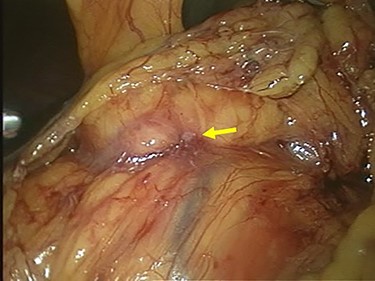

Chest and abdominal computed tomography (CT) showed no distant metastasis, but the tumor of the antrum was clearly visualized and was located close to the pancreatic head (Fig. 1). EGD revealed a large ulcerated lesion at the greater curvature of the antrum (Fig. 2). Hematoxylin and eosin staining of the biopsy specimen of the tumor confirmed a well-differentiated adenocarcinoma (tub1, tub2) (Fig. 3). The assessment of the HER2 expression by immunohistochemistry revealed the overexpression of HER2 (3+) in the biopsy tissue of the gastric tumor (Fig. 4).

Abdominal CT showed the tumor at the gastric antrum visualized as a thickened wall, suggestive of direct invasion to the pancreatic head (arrow).